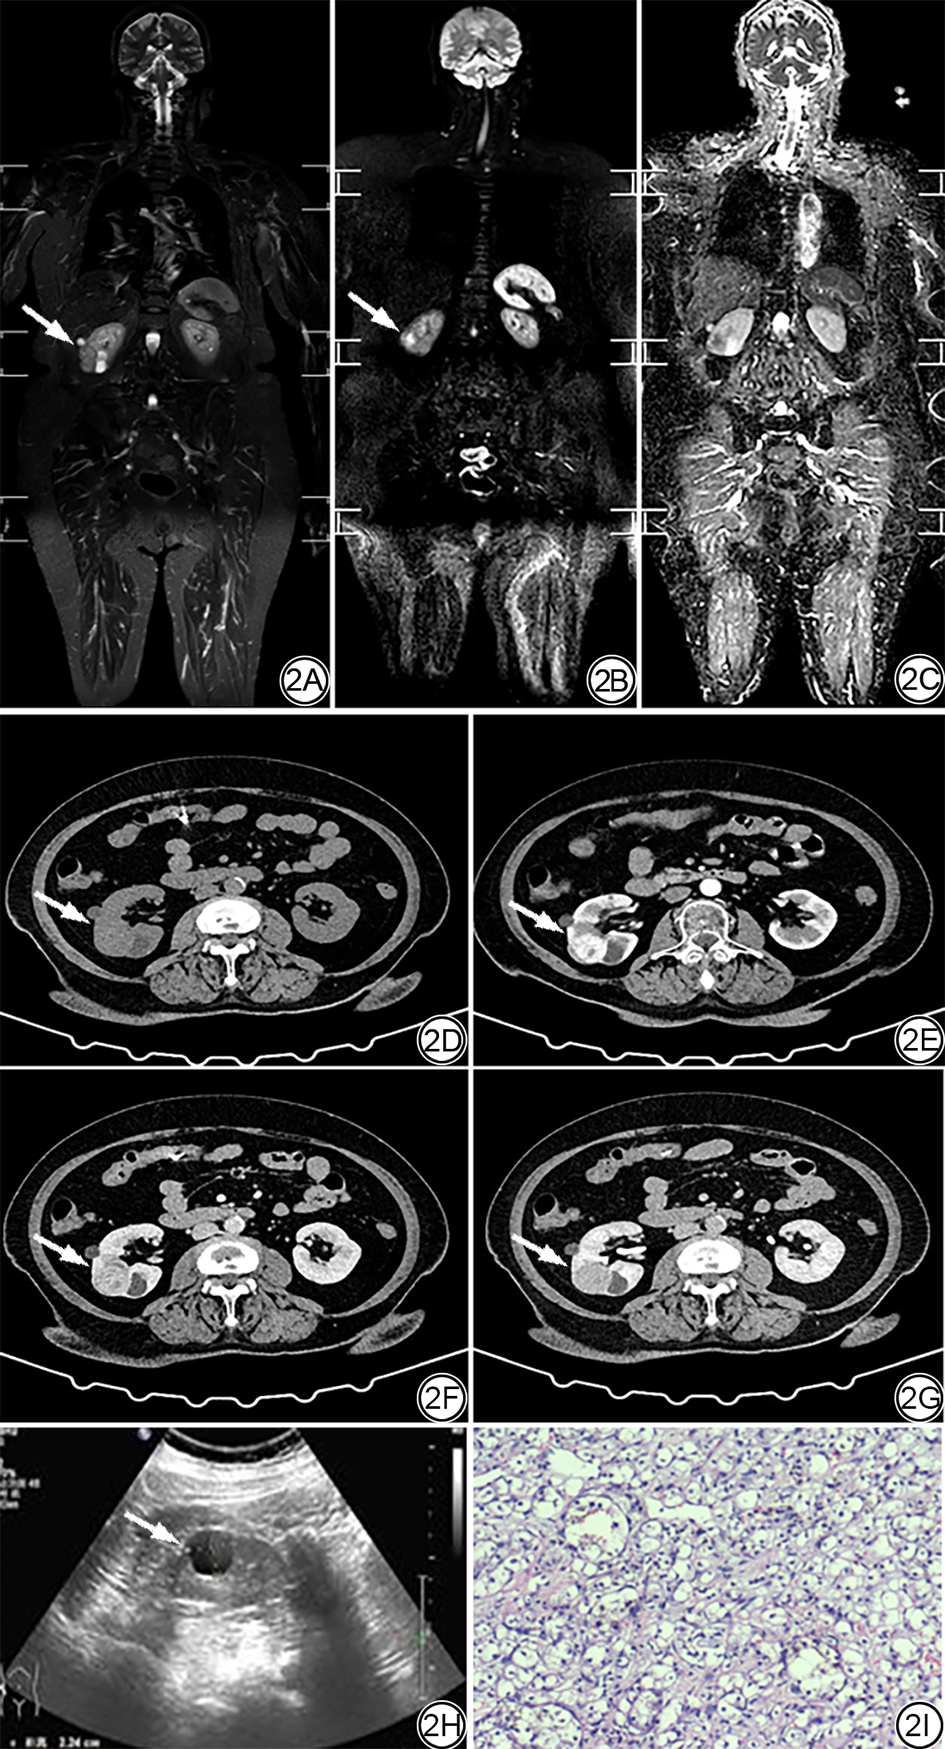

对有随访结果的116个显著病变的临床管理路径及最终结局进行归纳。极少部分病变(4/116,3.45%)因临床症状明显或影像提示恶性,最终接受了穿刺活检或手术切除:脑胶质瘤1例、脑膜瘤2例、肾透明细胞癌1例(图2)。但绝大多数(112/116,96.55%)通过常规影像学检查或随访被证实为良性或稳定性病变[如纵隔结节、肝脏海绵状血管瘤、脾脏血管瘤、胆系扩张、胰腺IPMN、肾脏错构瘤、子宫腺肌症、附件巧克力囊肿、骨岛、内生软骨瘤(图3)、臂丛神经水肿(图4)等]。

图2  女,66岁,右侧乳腺浸润性癌术后10年。2A~2C:WB-MRI图像;2A:T2WI-STIR序列显示右肾轮廓异常(箭);2B:DWI序列显示右肾下极弥散受限小肿块(箭);2C:ADC图对应区域明显低信号;提示该病变为显著偶发病变,恶性不排除;2D:该右肾病变CT平扫呈等密度(箭);2E~2G:CT增强扫描,皮质期及髓质期病灶不均匀强化(箭),延迟期呈稍低密度(箭);2H:超声未探及此病灶,仅见病灶旁囊肿(箭);2I:病理(HE ×100),巢状及腺泡状结构,核仁突出,为肾透明细胞癌。WB-MRI:全身磁共振成像;T2WI-STIR:短时反转恢复技术的T2加权成像;DWI:扩散加权成像;ADC:表观扩散系数。

Fig. 2  Female, 66-year-old, ten years postoperatively for right invasive breast cancer. 2A to 2C: WB-MRI image. 2A: T2WI-STIR sequence shows abnormal contour of right kidney (arrow). 2B: DWI sequence shows a small mass with limited diffusion in the lower pole of the right kidney (arrow). 2C: The corresponding area on the ADC map is obviously low signal. It is suggested that the lesion is a significant incidental lesion, and malignancy cannot be ruled out. 2D: The plain CT scan of the right kidney showed equal density (arrow). 2E to 2G: On enhanced CT scan, the lesions in cortical phase and medullary phase are unevenly enhanced (arrow), and the delayed phase showed slightly low density (arrow). 2H: The focus is not detected by ultrasound, only the cyst beside the focus is found (arrow). 2I: Pathology (HE ×100), nested and acinar structure, prominent nucleolus, clear cell carcinoma of kidney. WB-MRI: whole-body magnetic resonance imaging; T2WI-STIR: T2-weighted imaging with short-time inversion recovery technique; DWI: diffusion-weighted imaging; ADC: apparent diffusion coefficient.